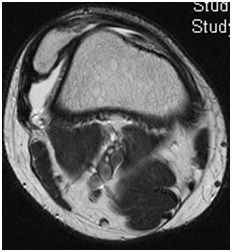

Dislocation of the patella occurs when the patella moves out of the patellofemoral groove. It is most commonly caused by a twisting injury or a direct blow to the knee. Factors that increase the chance of the patella dislocating include patella alta (when the patella is too high, bringing it out of the groove), trochlear dysplasia (in which the trochlear groove is shallow or domed the other way), weakness or abnormalities of the muscles that help to hold the patella in place and an abnormal alignment of the bones of the leg. When the patella dislocates, all of the soft tissue on the inner side of the patella is stretched or torn, including a ligament called the medial patellofemoral ligament (MPFL) which usually helps to hold the patella in. Up to half of people who dislocate their patella will have further dislocations. They may also feel that the patella is unstable, even if it does not completely dislocate.